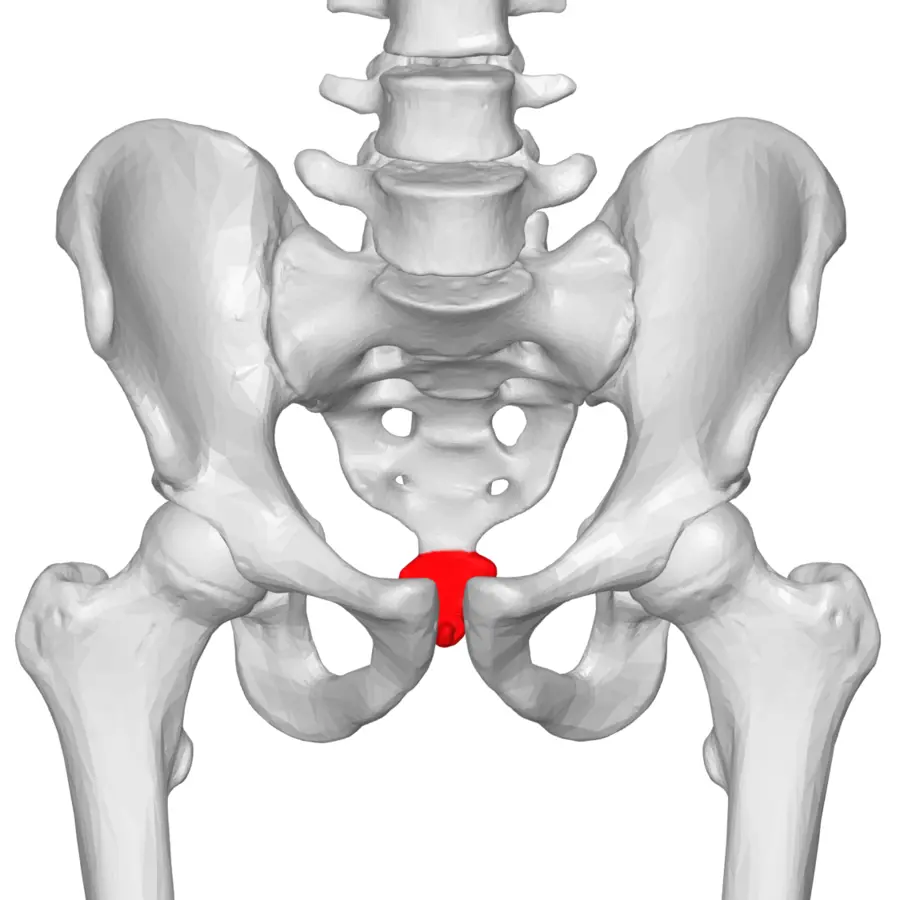

Trtica, ili coccyx na latinskom, predstavlja završni dio kralježnice i često se naziva “repna kost“. Iako naziv sugerira da se radi o jednoj kosti, trtica se zapravo sastoji od 3 do 5 zasebnih kralježaka, koji su kod različitih osoba više ili manje spojeni. Trtica je povezana s križnom kosti (sakrum) preko sakrokocigealne zglobne veze, koja uključuje i hrskavični disk te male zglobove s obje strane.

U zglobu između trtične i križne kosti moguć je blagi pokret, najčešće pomak prema naprijed prilikom sjedenja i opterećenja. Funkcionalno, trtica zajedno s lijevom i desnom kvrgom sjedne kosti tvori svojevrsni “tronožac”, koji podupire tijelo pri sjedenju i ravnomjerno raspoređuje težinu.

Trtica je također mjesto gdje su pričvršćeni brojni mišići i ligamenti zdjelice, koji pomažu pri stabilnosti zdjeličnog pojasa i podršci unutarnjim organima. Zanimljivo, riječ coccyx potječe iz grčkog jezika i znači “kljun kukavice”, jer oblikom sa strane podsjeća na kljun ove ptice.